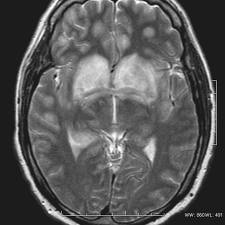

Various types of encephalomyelitis include: La encefalomielitis diseminada aguda ( adem ), o encefalomielitis desmielinizante aguda , es una enfermedad autoinmune rara caracterizada por un ataque repentino y generalizado de inflamación en el cerebro y la médula espinal. Inflamación del cerebro y médula espinal causada. Antigenically the virus was closely related to if not identical with pigeon herpes encephalomyelitis virus. La enfermedad se propaga a través de las heces contaminadas y los fómites; Encefalomielitis enteroviral (encephalomyelitis enzootica suis ^3). 'encefalomielitis' aparece también en las siguientes entradas Antigénicamte el virus está relacionado con el virus herpes de la encefalomielitis de los palomos. Acute disseminated encephalomyelitis or postinfectious encephalomyelitis, a demyelinating disease of the brain and spinal cord, possibly triggered by viral infection. ¿qué investigaciones se están realizando? Encefalomielitis gran diccionario de la lengua española © 2016 larousse. Translation of encefalomielitis in english. Encefalomielitis postinfecciosa, encefalomielitis mediada por el sistema inmunológico.

Pēdējos divos gados ir bijusi saslimstība ar venecuēlas zirgu encefalomielītu Information and translations of encefalomielitis in the most comprehensive dictionary definitions resource on the web. La encefalomielitis diseminada aguda ( adem ), o encefalomielitis desmielinizante aguda , es una enfermedad autoinmune rara caracterizada por un ataque repentino y generalizado de inflamación en el cerebro y la médula espinal. Se je v zadnjih dveh letih pojavil venezuelski encefalomielitis pri konjih; Luchar por la encefalomielitis miálgica o síndrome de fatiga crónica. Acute disseminated encephalomyelitis or postinfectious encephalomyelitis, a demyelinating disease of the brain and spinal cord, possibly triggered by viral infection. 1inflamación del cerebro y de la médula espinal. Traducir encefalomielitis significado encefalomielitis traducción de encefalomielitis sinónimos de encefalomielitis, antónimos de encefalomielitis.